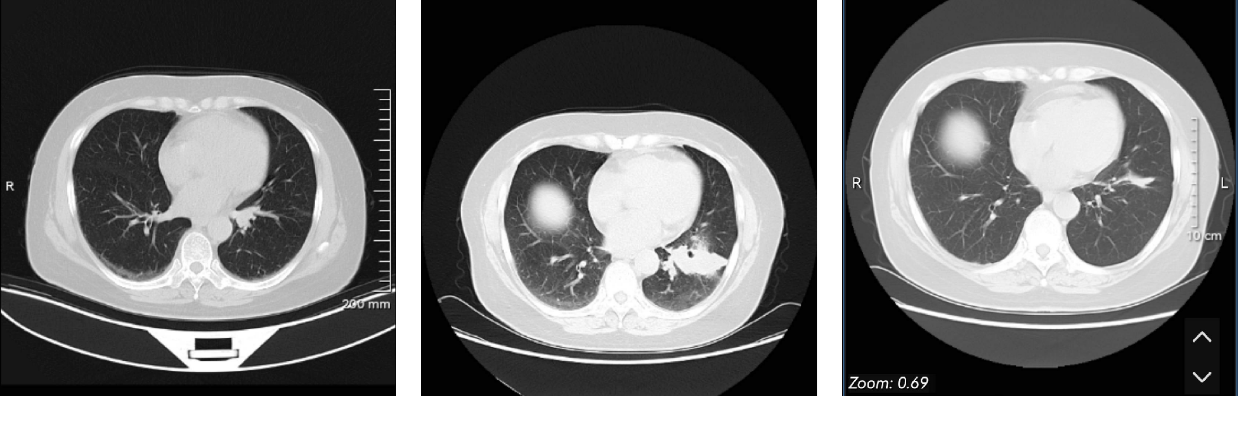

7月确诊,转至天津肿瘤,经PETCT等一系列检查,定为3a期,肿瘤1.2*1.8(pet测量,ct不曾报过大小,可能不好测量),7区隆突下淋巴怀疑转移。

于三化第十天,做ct平扫(转院需要),报告显示最初原发灶软组织结节影消失…图片

立即赶往中科院肿瘤医院,经过一系列检查,我们确实达到了影像cr,随后进行手术

手术很顺利,不到两周大病理出来了,但遗憾的是,手术病理中,我们没有达到cr。大病理原发灶未见癌,但清扫的27个淋巴结中,同侧肺门淋巴有一个转移,分期2期。